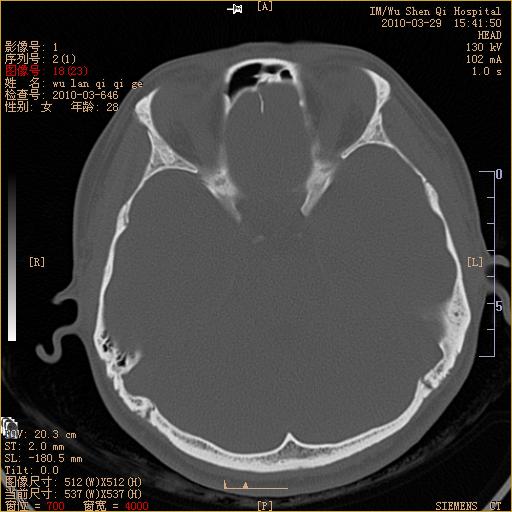

标题: CT25398:女,左耳流脓两年余,带有异物 [打印本页]

标题: CT25398:女,左耳流脓两年余,带有异物

左侧中耳乳突炎,不排除胆脂瘤形成。

左侧中耳乳突炎,胆脂瘤形成。

左侧中耳乳突炎,不排除胆脂瘤形成

1)左侧慢性中耳乳突炎并肉芽肿(或胆脂瘤)形成。2)考虑左侧颞骨慢性炎症伴骨质增生硬化,不排除骨纤。